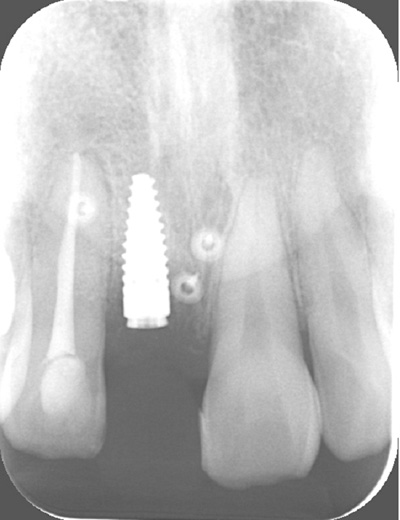

| 年代・性別 | 30代 女性 |

|---|---|

| 主訴 | 左上の乳歯がグラグラしてきた |

| 治療期間 | 約12ヶ月 |

| 費用 | 550,000円 |

| 治療内容 | インプラント、骨造成、セラミック修復 |

| 治療に伴うリスク | インプラント周囲炎 セラミックの破折、脱離 |